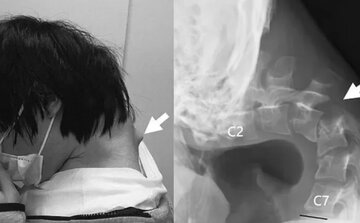

این مرد جوان ژاپنی بیشتر وقت خود را صرف بازی با تلفن همراه کرده و به همین دلیل، گردن او ساعتها بهطور خمیده باقی مانده بود. درنتیجه علاوهبر ضعف در گردن، برآمدگی بزرگی هم در قسمت پشت گردن او مشاهده میشد، بهطوریکه او دیگر نتوانست سرش را بلند کند.

اسکنهای گردن او خبر از تغییر شکل و جابهجایی مهرههای گردن میداد و همچنین در قسمت بالایی ستون فقرات او، بافت زخمی و صدمهدیدهای مشاهده میشد. تمام این مشکلات نشان میداد که گردن بهمدت طولانی در حالت کشیده و غیرطبیعی قرار گرفته است.